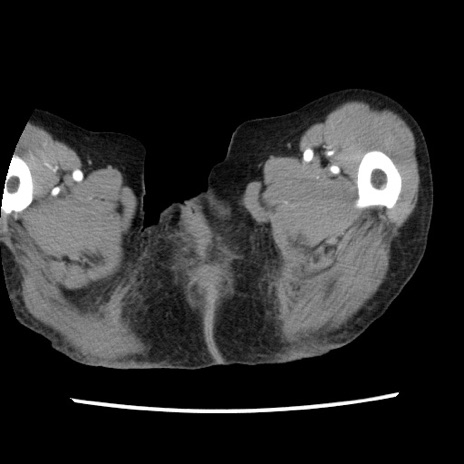

症例1(横断像)

症例

【症例】80歳代女性

【主訴】腹痛

【現病歴】8時間前から腹痛あり来院。

【既往歴】糖尿病、脂質異常症、子宮体癌にて子宮全摘術

【身体所見】意識清明・会話良好だが腹痛で苦悶様、全腹部にわたって反跳痛と圧痛あり

【データ】WBC 13600、CRP 0.14、LDH 224、CK 90